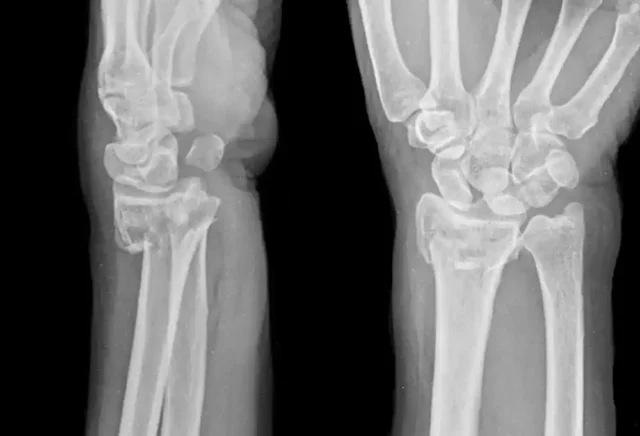

Tedavisinde problemli bölge alçıya alınabilir. Tedavi sürecinde hasta kesinlikle yumuşak ve koruyucu ayakkabıları tercih etmelidir. Bu hastalığın tanısı koyulurken kullanılan en etkili yöntem, MRI’ dır. Bahsedilen uygulamaların tümü cerrahi dışı yöntemlerdir. Ancak hasta bu yöntemlerden herhangi birisine cevap vermezse cerrahi uygulamalara başvurulabilir.